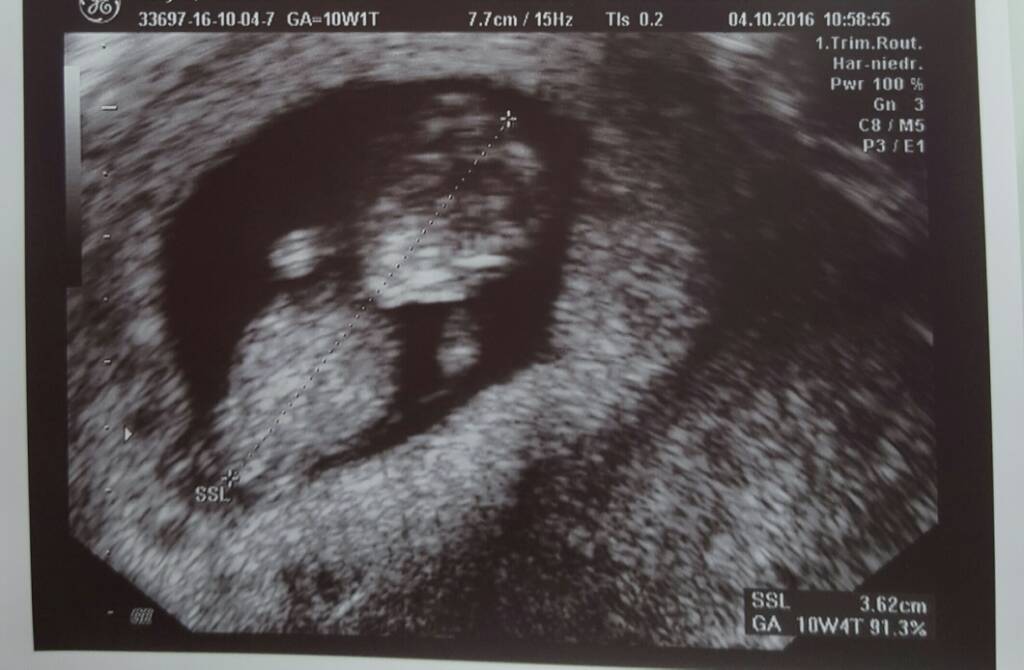

Zobacz załącznik 776387

A to moje kropkiBliźnięta dwukosmówkowe, według OM 7 tyg 2 dni, według USG 6 tyg 5 dni